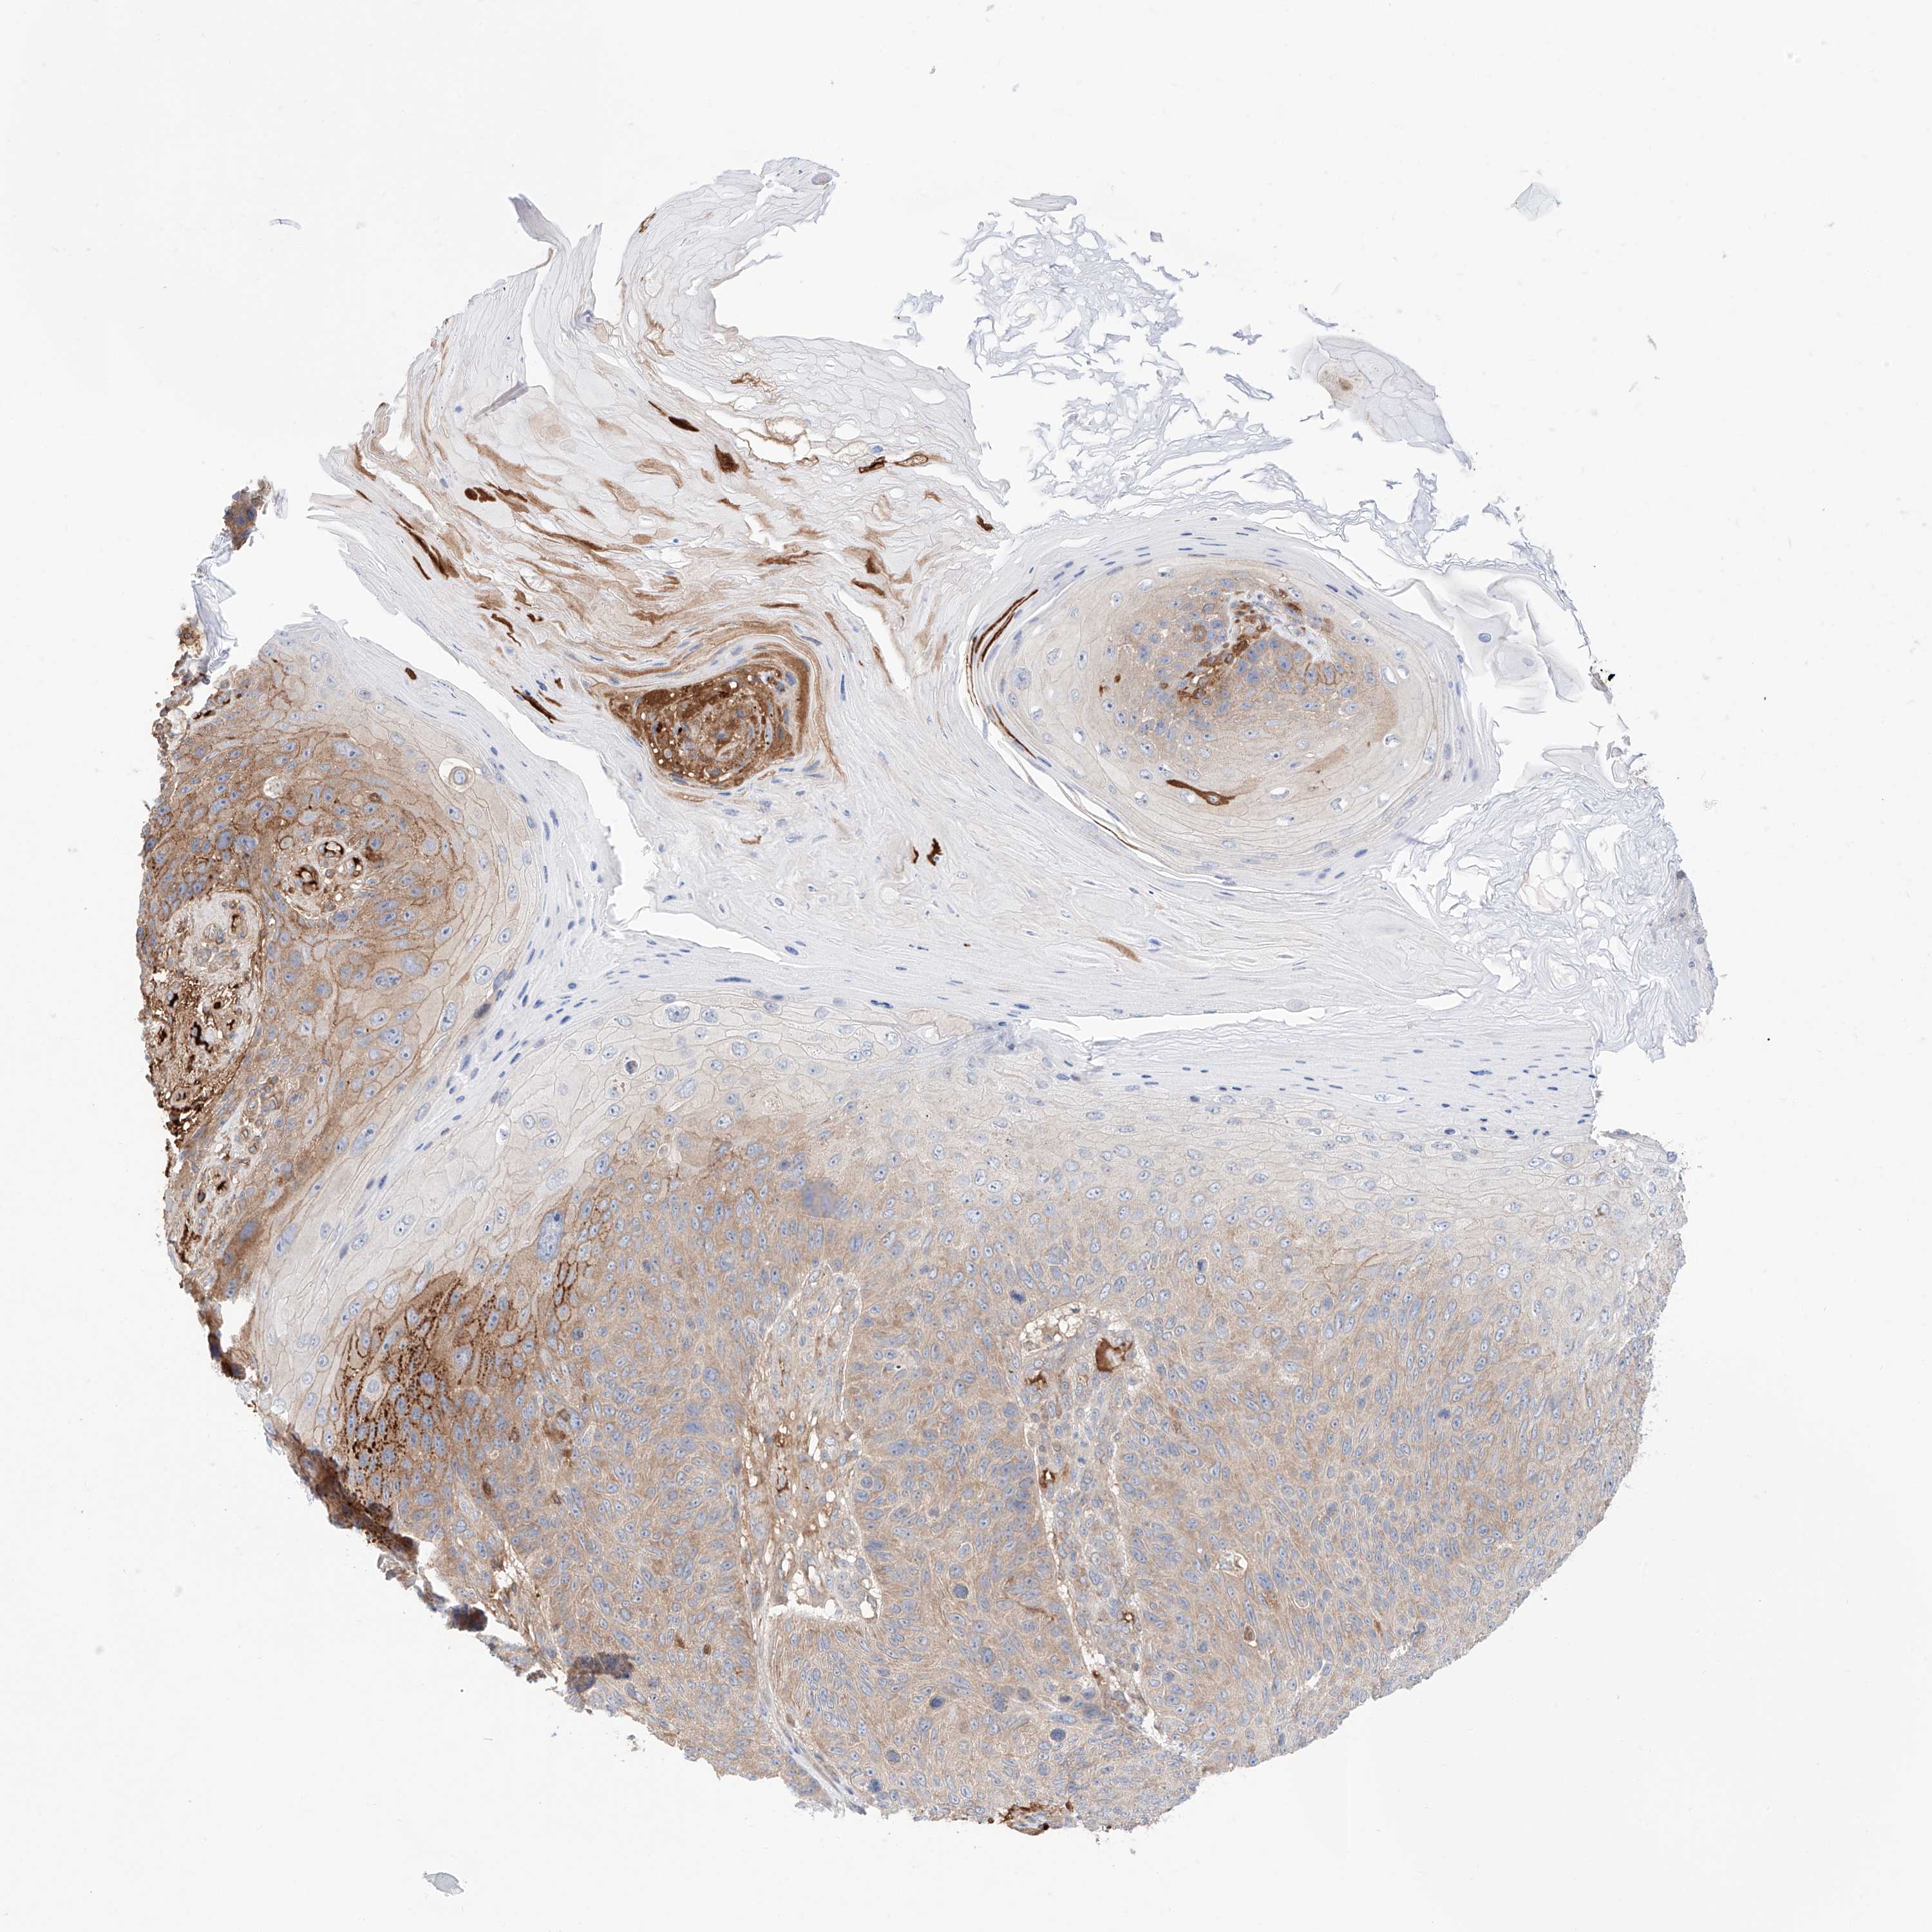

SKIN CANCER - Protein expressioni

A mouse-over function shows sample information and annotation data. Click on an image to view it in a full screen mode. Samples can be filtered based on level of antibody staining by selecting one or several of the following categories: high, medium, low and not detected. The assay and annotation is described here.

Antibody stainingi

Antibody staining in the annotated cell types in the current human tissue is reported as not detected, low, medium, or high, based on conventional immunohistochemistry profiling in selected tissues. This score is based on the combination of the staining intensity and fraction of stained cells.

Each image is clickable and will lead to virtual microscopy that enables deeper exploration of all samples and also displays staining intensity scores, fraction scores and subcellular localization as well as patient and tissue information for each sample.

Antibody HPA030646

Staining

High

Medium

Low

Not detected

Intensity

Strong

Moderate

Weak

Negative

Quantity

>75%

75%-25%

<25%

None

Location

Nuclear

Cytoplasmic/membranous

Cytoplasmic/membranous,nuclear

Squamous cell carcinoma, NOS